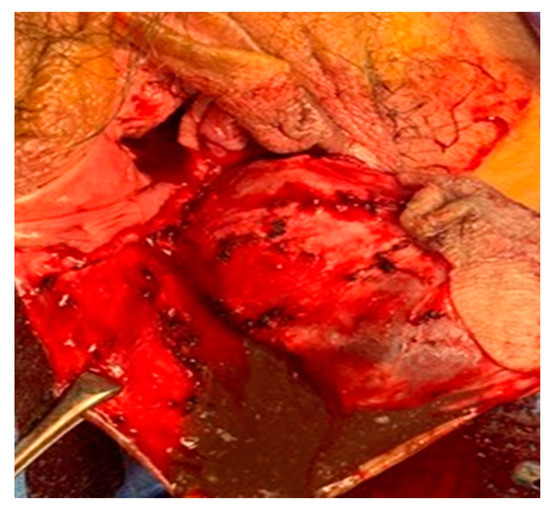

2. Case